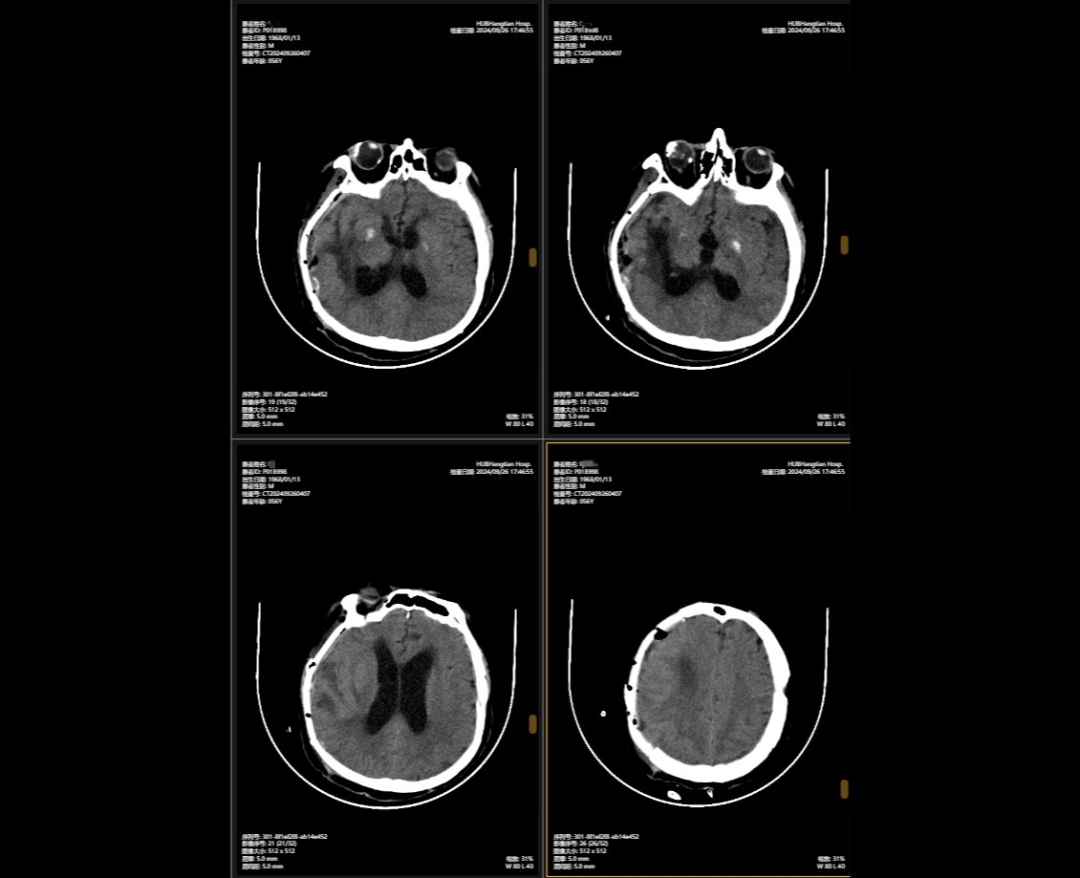

2024年5月,56歲的李先生(化名)不幸遭遇嚴重車禍,當場昏迷,生命垂危。他被緊急送往湖北航天醫(yī)院后,檢查結果讓所有人心頭一緊:他的頭部受到嚴重撞擊,不僅有多處出血,腦組織也有挫傷,甚至連呼吸心跳的“總司令部”——腦干都受了傷。除此之外,還有顱骨、頸椎和多處肋骨骨折,情況萬分危急。

李先生頭部的多處損傷就像一顆顆“炸彈”,隨時可能危及生命。航醫(yī)神經(jīng)外科團隊接診后,面對如此復雜的顱內(nèi)損傷,神經(jīng)外科主任陳義勇當機立斷,一方面做好周密的手術準備,一方面迅速展開多學科會診,多學科團隊緊急集合,反復協(xié)商探討,一同制定了詳盡手術方案。手術方案確認后,神外團隊爭分奪秒,第一時間為李先生實施了顱內(nèi)多發(fā)血腫清除術+右側開顱顱內(nèi)減壓+去骨瓣減壓術+左側硬膜外血腫清除術+矢狀竇破裂止血術。手術過程中,醫(yī)生們精準操作,成功止住了出血,最大限度地保護了正常腦組織,為李先生贏得了生的希望。

顱骨缺損修補術前術后對比